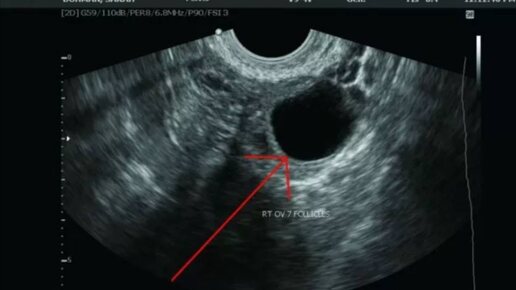

КАК ОПРЕДЕЛИТЬ БЫЛА ОВУЛЯЦИЯ ИЛИ НЕТ 🤔: Овуляция - это выход яйцеклетки из яичника в маточную трубу в результате разрыва доминантного фолликула Достоверные методы: 📍Фолликулометрия. При цикле 28-30 дней на 10-11 день цикла выполняется УЗИ для определения доминантного фолликула (более 10 мм в диаметре ) и далее контролируем каждые 2 дня до овуляции. Далее по узи за 7 дней (19-21 день цикла при его продолжительности 28-30 дней )до предполагаемой менструации надо оценить наличие желтого тела ...